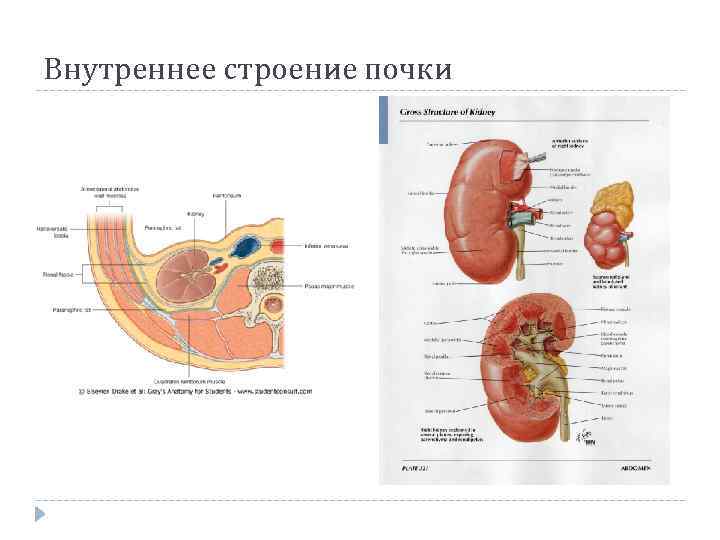

Внутреннее строение почки

Внутреннее строение почки

Внутреннее строение почки

Внутреннее строение почки